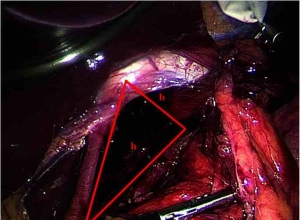

荧光造影在腹腔镜胆囊切除术 — 最初的加拿大经验Fluorescent cholangiography in laparoscopic cholecystectomy- the initial Canadian experienceAbstractBACKGROUND:Bile duct injury remains a worrisome compli ...

倒钩缝合术在腹腔镜胆囊切除术中胆管损伤修复中的应用——附2例报告Effectiveness of a barbed suture in the repair of bile duct injury during laparoscopic cholecystectomy- Report of two casesAbstract摘要IN ...